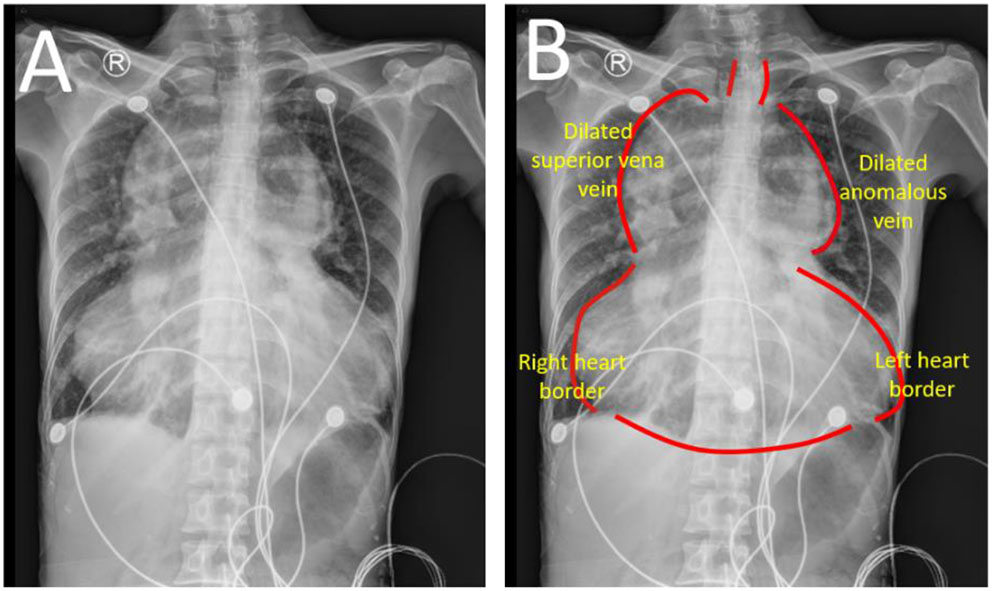

Chest radiograph showed an increased cardiothoracic ratio at.95 with no evidence of heart failure. It found that both lung fields and costophrenic angles are clear. The cardiac enlargement resembles a “calabash” configuration (Figure 1). The mediastinum is widened in relation to the heart border.

Chest radiograph (A,B). A huge “calabash” heart presented as appearance according to chest radiograph. The mediastinum is obviously in relation to heart border. TAPVR, total anomalous pulmonary venous return.

The “calabash” configuration on the chest radiograph is uncommonly observed in supracardiac TAPVR. The SVC and right heart dilation formed a right-sided configuration and the dilated innominate vein mainly consists of this left-sided configuration. There is also a non-specific appearance of the chest radiograph in some patients, and then used as such CT scan and echocardiography for accurate diagnosis of TAPVR. This patient was firstly reported as “calabash” appearance on the chest radiograph and was diagnosed by CT scan and echocardiography. A cardiac CT scan presented venous system enlargement, but also aortic system disuse atrophy. Disuse atrophy probably resulted from a reduction of aortic effective blood circulation, while right heart dilation is caused by excessive pulmonary blood circulation. Cardiac hemodynamic assessment in the patient showed no pulmonary hypertension and for further surgical repair.